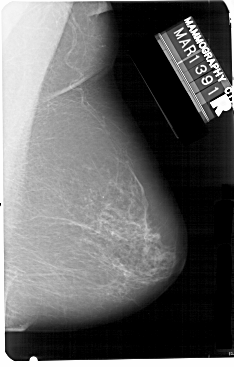

A_1341_1.LEFT_MLO

LEFT_MLO LINES 5491 PIXELS_PER_LINE 3631 BITS_PER_PIXEL 12 RESOLUTION 43.5 OVERLAY